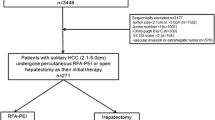

This retrospective study was approved by our institutional review board, and informed written consent from patients was waived. Between September 2007 and December 2014, 439 patients underwent a first NTMBP-RFA procedure in our center for the treatment of HCC. Patients who had previously been treated or were simultaneously being treated with ablation techniques other than NTMBP-RFA, those for whom pre-therapeutic imaging was not available, and patients treated for a recurrence after liver transplantation (but not after liver resection), were all excluded from the study (Fig. 1). Pre-therapeutic multiphasic contrast-enhanced CT scan or MRI of the remaining 375 patients were analyzed in order to locate their tumors.

Among these 375 patients, 97 (25.9%) had one or up to three S-HCC, defined as an HCC nodule abutting the superficial liver capsule. Three patients with infiltrative HCC and five patients with a subcapsular tumor larger than 5 cm were excluded. The imaging studies of the remaining 89 patients with S-HCC were then reviewed by an interventional radiologist (OSe) with more than 15 years of experience in the percutaneous ablation of liver tumors, in order to select those with S-HCC not puncturable via the non-tumorous liver parenchyma (Fig. 2). Finally, 59 S-HCCs (located in Couinaud segments 3, 4, 5, 6 and 8) in 58/89 patients (65.2%) were considered not directly puncturable via the non-tumorous parenchyma and were included in the analysis. The diagnosis of HCC was based on the typical imaging pattern defined by EASL guidelines [22]. All treatment decisions were taken by a multidisciplinary tumor board gathering hepatologists, oncologists, radiologists, pathologists and liver surgeons.